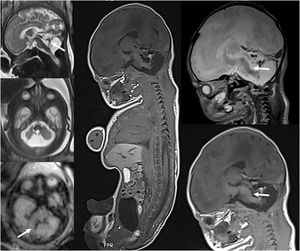

Advances in magnetic resonance imagingIn recent years, there have been significant advances in magnetic resonance imaging (MRI), especially in terms of reducing acquisition times. Rapid MRI techniques reduce acquisition times enough to avoid sedation, and is most commonly used for brain imaging, but it can also be used for assessment of acute abdomen and musculoskeletal infections. The Dixon technique achieves uniform fat suppression and also makes it possible to obtain images with and without fat suppression from a single acquisition. Diffusion tensor imaging (DTI) allows quantification of anisotropic diffusion in various directions, and subsequent construction of anisotropy maps representing the direction of tracts (tractography), which can depict microstructural changes in the brain, including physiological changes caused by myelination and brain development, the effect of various disorders, and post-treatment changes. This technique helps neurosurgeons reduce morbidity by resecting as much of the mass as possible, preserving the most important white matter tracts, such as corticospinal tract fibers, responsible for motor function, or the arcuate fasciculus, involved in language. Arterial spin labeling perfusion MRI is a perfusion method that does not require administration of gadolinium tracer but rather uses the water in blood as an endogenous tracer, thus offering the advantage of being noninvasive. It can depict perfusional changes in the brain resulting from various disorders or anomalies, such as strokes, seizures, complicated migraines, or brain neoplasms (Fig. 2). Magnetic resonance spectroscopy (MRS) provides metabolic information complementary to neuroanatomic images and is particularly useful in cerebral neoplasms, contributing to tumor grading and the assessment of treatment response. Functional MRI (fMRI) uses blood oxygenation level-dependent and its main clinical application is in presurgical planning before resection of lesions such as brain tumors, vascular malformations, or epileptogenic foci near the eloquent cortex. The eloquent areas of the brain interrogated most commonly include motor areas, language areas and visual areas, typically via various task-based fMRI paradigms. Susceptibility weighted imaging is a 3D high-spatial-resolution gradient-echo MRI sequence sensitive to the magnetic properties of blood products, calcifications and iron that can be used for detection of microhemorrhages and differentiate them from calcifications or to visualize anomalous vascularization in high-grade tumors.3

(A) Transfontanellar ultrasound performed on the first day of life in a full-term newborn with severe hypoxia-ischemia showing bilateral central gray matter injury (arrows). (B) Head MRI performed 4 days post birth showing bilateral central gray matter injury in T1- and T2-weighted images, with restricted diffusion and evidence of increased perfusion in arterial spin labeling (arrows), which has been associated with a poor prognosis.